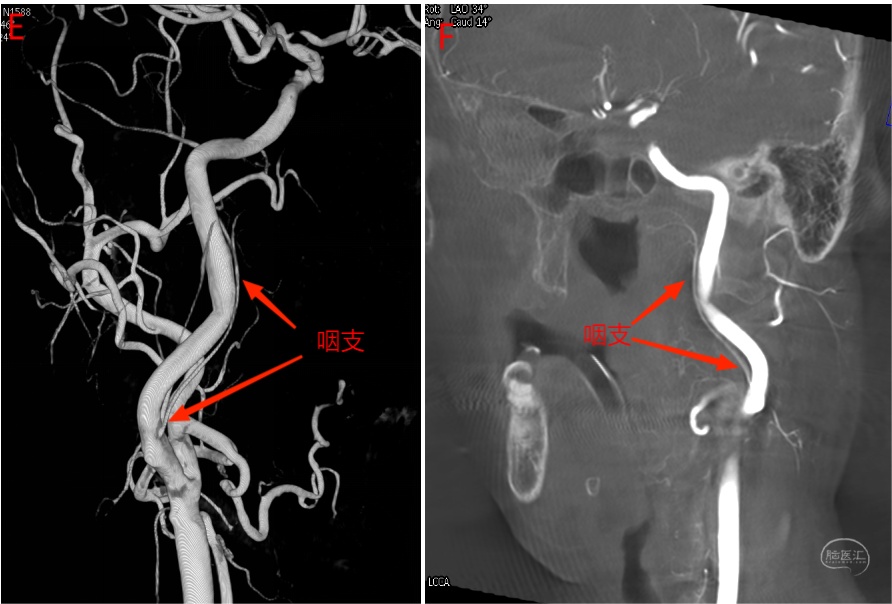

右侧颈内动脉闭塞患者,右侧咽升动脉自颈外动脉发出,左侧咽升动脉咽支自颈内动脉发出,神经脑膜支自枕动脉发出。

图13 左侧颈总动脉正位(C)及侧位(D)造影。由于颈内动脉遮挡,咽升动脉在侧位显示不清。正位可见咽升动脉咽支自颈内动脉发出,神经脑膜支在枕动脉发出(详见下图3D及Xper CT)。

图14 左侧颈总动脉3D(E)及Xper CT重建(F)图像。可见咽升动脉咽支自颈内动脉发出,供血至咽部。

图15 左侧颈总动脉3D(G)及Xper CT(H)图像。可见咽升动脉神经脑膜支自枕动脉发出,向上走形进入舌下神经管。